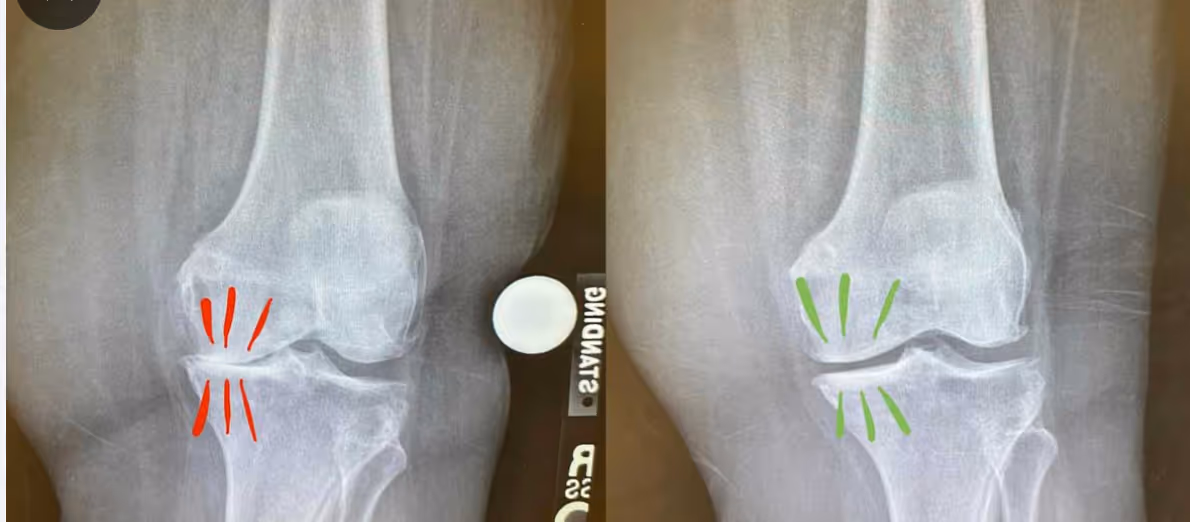

"Was die meisten nicht verstehen: Es ist ein komplexes Zusammenspiel verschiedener Faktoren", erklärt er. "Die Viskosität der Gelenkflüssigkeit spielt eine entscheidende Rolle. Wenn diese sich verändert, wird sie zähflüssiger, was die Beweglichkeit einschränkt. Gleichzeitig kann sich der Blutfluss zu den Gelenken reduzieren - ein teuflischer Kreislauf beginnt."

"In meiner Praxis sehe ich bei vielen Arthrose-Patienten dasselbe Muster", fährt Dr. Wibmer fort. "Patienten, die zeitweise kaum Beschwerden haben, kommen plötzlich mit starken Schmerzen zu mir."

Die verminderte Durchblutung führt dazu, dass weniger Nährstoffe in die Gelenke gelangen, was die Schmerzen noch verstärkt. Es ist ein Teufelskreis, den herkömmliche Behandlungsmethoden oft nicht durchbrechen können."